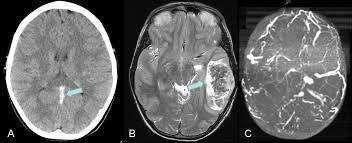

Imaging of cerebral venous thrombosis.

We aimed to update the previous european federation of neurological societies guidelines using a clearer and. Silvis, sini hiltunen, et al. (a) ct scan of head with contrast (1 mm axial) showing left transverse sinus thrombosis. Thrombosis of cerebral veins and venous sinuses is a rare disease, which accounts for less than 1% of all cases of stroke. Cerebral venous sinus thrombosis (cvst) is the presence of a blood clot in the dural venous sinuses, which drain blood from the brain. Cerebral venous sinus thrombosis created by paul young 22/11/07. H u h n a. Thrombosis of the venous channels in the brain is an uncommon cause of cerebral infarction relative to arterial disease, but it is an important consideration because of its potential morbidity.

Imaging of cerebral venous thrombosis. Cerebral venous thrombosis (cvt), also called cerebral venous sinus thrombosis (cvst), is a cerebrovascular disease with diverse clinical manifestations that often affects young adults, women of childbearing age, and children. September 6, 2020 by josh farkas. Cerebral venous sinus thrombosis occurs when a blood clot forms in the brain's venous sinuses. A thrombotic obstruction of the cerebral veins and/or related anatomical structures (dural sinuses) which drain blood from the brain. And a third patient had thrombosis of the deep medullary veins. A transcranial doppler ultrasound study. Characteristic, but rare, is the occurrence of unilateral hemispheric. Common subtypes include transverse sinus thrombosis and superior sagittal sinus. Cerebral venous sinus thrombosis is a rare entity. Valdueza j.m., schmierer k., mehraein s., einhдupl k.m. Cerebral venous sinus thrombosis (cvst) is the presence of a blood clot in the dural venous sinuses, which drain blood from the brain. See that article for a discussion of that specific clinical entity.